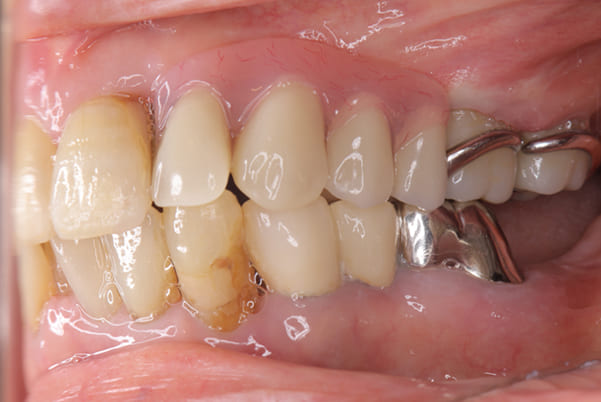

入れ歯が沈み込むことを防止するストッパーがない入れ歯を装着されていたため、お食事により入れ歯が沈み込みお痛みがでている状態でした。

笑った際に、太いバネが左右に見えるため、あまり大きく笑うことを避けていらっしゃいました。

作製した入れ歯は、お食事の際に入れ歯の沈み込みを予防するため、適切なストッパーを付与することで、入れ歯は沈み込まなくなり、お痛みは消失しました。

右下のバネの位置は後ろに、左下のバネは見えづらい形態のバネを用いる設計とすることで笑った際にバネが見えないようになり、気にされることはなくなられました。

裏側の見えない部分は金属を用いることで、お食事の際の入れ歯の動き、沈み込みを抑えお痛みがでづらく、入れ歯の動きが抑制されることで、長期的に残りの歯に負担のかかりにくい設計としました。